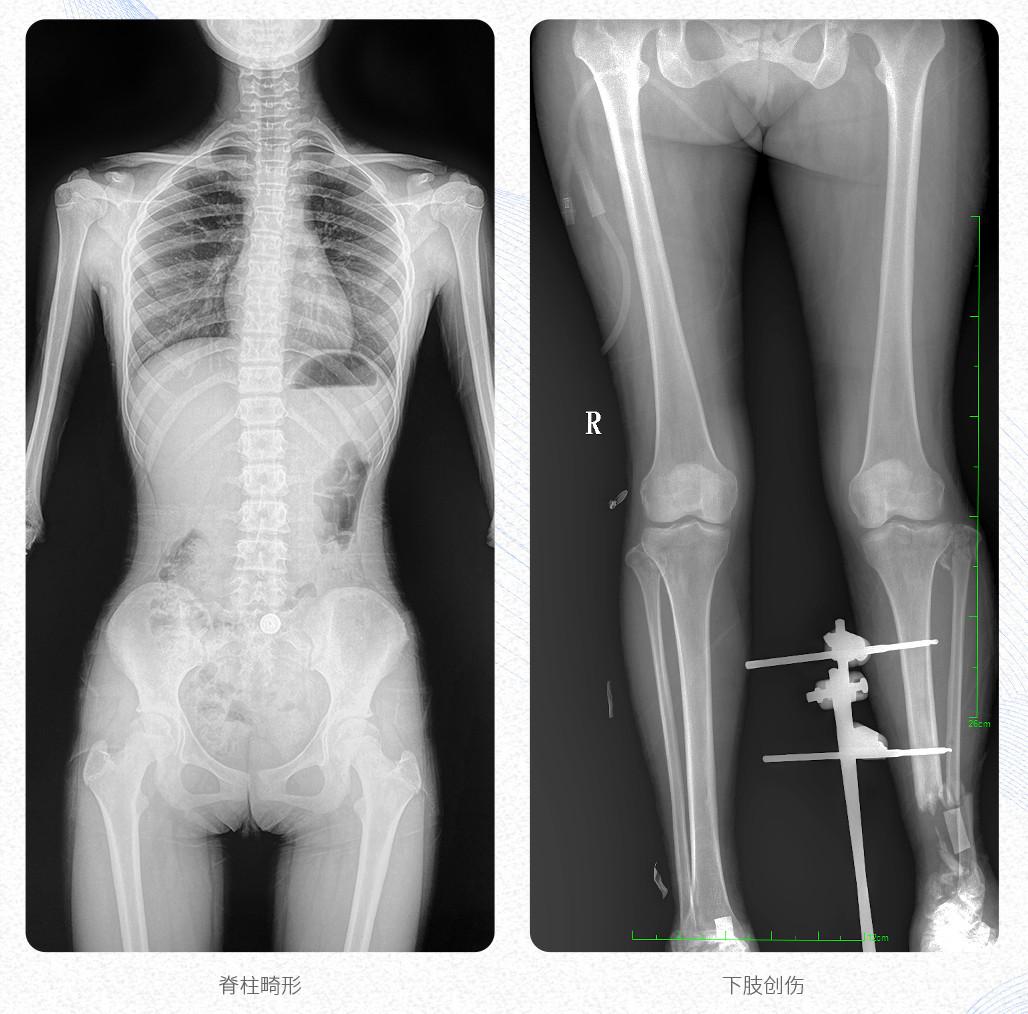

臨床應(yīng)用:支持全脊柱攝影、雙下肢攝影、脊髓造影、復(fù)雜創(chuàng)傷、人工關(guān)節(jié)置換、關(guān)節(jié)損傷的修復(fù)重建等大視野臨床應(yīng)用。

17"*34"有效視野,是市面大尺寸平板的2倍,一次成像不拼接。相較于多張攝影再軟件拼接的DR設(shè)備,PLX8600解決了拼接圖像存在密度不均勻,拼接處圖像配準(zhǔn)和放大效應(yīng)等問(wèn)題,給臨床帶來(lái)了真正的大視野影像解決方案,高清畫質(zhì),準(zhǔn)確成像不失真,可一次性覆蓋全脊柱或雙下肢影像。PLX8600大視野平板動(dòng)態(tài)DR攝影速度快,患者可以更快的完成檢查,且單次攝影輻射劑量是常規(guī)多張攝影再軟件拼接DR的1/2或1/3,低劑量給患者更多關(guān)愛(ài)。

PLX8600大視野平板動(dòng)態(tài)DR可在低輻射劑量下獲得患者站立位、臥位的高質(zhì)量影像。搭載自主研發(fā)的圖像均衡處理系統(tǒng),能夠很好的均衡人體不同厚度組織的影像,視野大,圖像清晰,層次豐富。